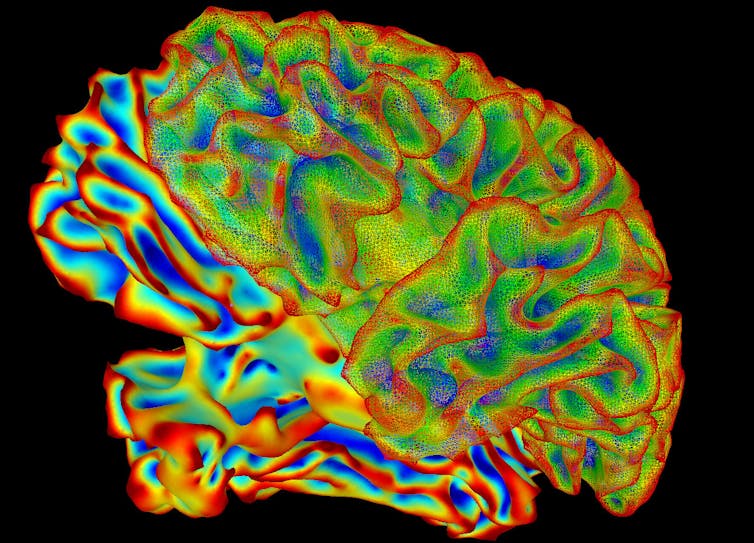

Pour employer une analogie météorologique, cela revient à décrire l’atmosphère non plus en fonction des molécules qui la composent, mais en termes de températures, pressions et vélocité de l’air. Un tel modèle est calculable à l’échelle du cerveau entier, et fournit une description interprétable des mécanismes de l’activité neuronale. Qui plus est, un tel modèle peut être enrichi par les modèles résultant des données empiriques collectées via l’imagerie cérébrale notamment. Il peut en retour être utilisé pour générer des données simulées, et vérifier si celles-ci sont effectivement en accord avec les observations.

La personnalisation des simulations est l’un des aspects les plus excitants de ce type de recherche. Il est en effet possible de façonner les modélisations cérébrales en utilisant des données structurelles acquises empiriquement, après avoir analysé par IRM le cerveau d’un individu donné par exemple. Autrement dit, la forme du cerveau et la connectivité des neurones d’une personne peuvent être utilisées pour façonner un réseau cérébral qui lui sera propre.